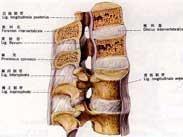

椎体爆裂骨折

628健康网为您分享有关椎体爆裂骨折的症状,椎体爆裂骨折的治疗方法,椎体爆裂骨折的预防知识,椎体爆裂骨折的症状图片,椎...

椎弓结核

628健康网为您分享有关椎弓结核的症状,椎弓结核的治疗方法,椎弓结核的预防知识,椎弓结核的症状图片,椎弓结核吃什么药,椎...

椎管内结核肉芽肿

628健康网为您分享有关椎管内结核肉芽肿的症状,椎管内结核肉芽肿的治疗方法,椎管内结核肉芽肿的预防知识,椎管内结核肉芽...

胸椎后纵韧带骨化症

628健康网为您分享有关胸椎后纵韧带骨化症的症状,胸椎后纵韧带骨化症的治疗方法,胸椎后纵韧带骨化症的预防知识,胸椎后纵...

胸椎椎管狭窄症

628健康网为您分享有关胸椎椎管狭窄症的症状,胸椎椎管狭窄症的治疗方法,胸椎椎管狭窄症的预防知识,胸椎椎管狭窄症的症状...

下腰椎不稳症

628健康网为您分享有关下腰椎不稳症的症状,下腰椎不稳症的治疗方法,下腰椎不稳症的预防知识,下腰椎不稳症的症状图片,下...

移行脊椎

628健康网为您分享有关移行脊椎的症状,移行脊椎的治疗方法,移行脊椎的预防知识,移行脊椎的症状图片,移行脊椎吃什么药,移...